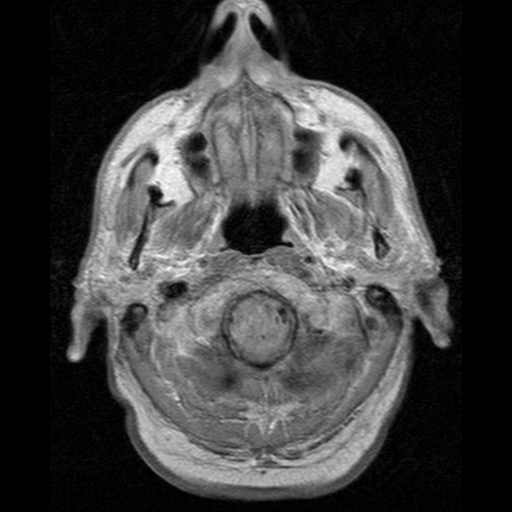

Более 30 миллионов людей в мире, подавляющее большинство из которых старше 65 лет, предположительно страдают болезнью Альцгеймера. Адуканумаб подходит пациентам моложе 80 лет и с начальной стадией болезни. Потребуется также установить точный диагноз при помощи детального МРТ-сканирования. В последние 10 лет рассматривались свыше ста средств лечения болезни Альцгеймера, но ни одно себя не оправдало.